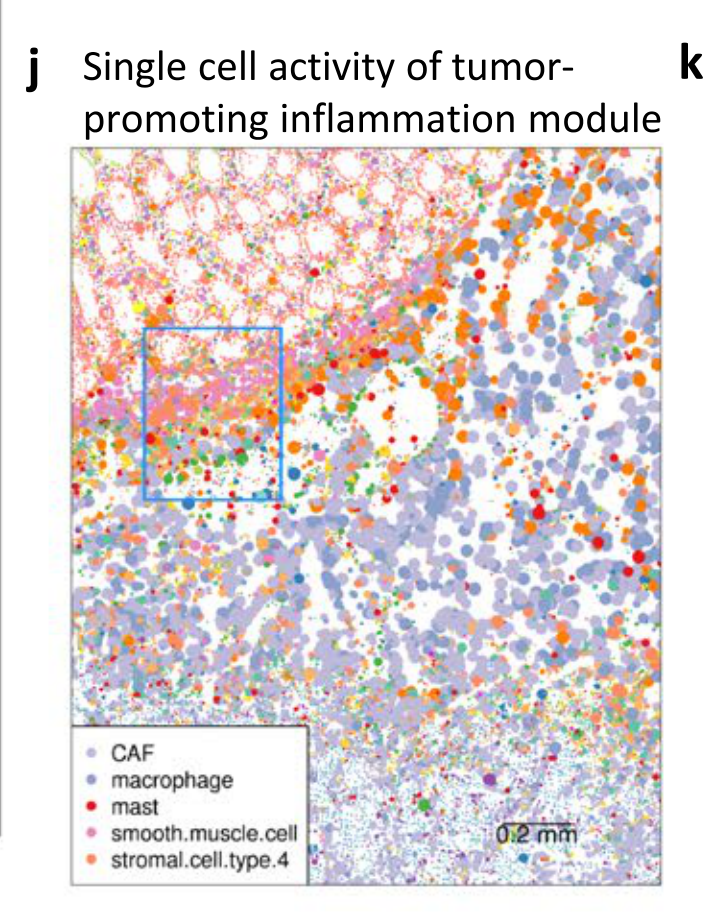

What is the raw visual evidence for the subcellular localization of the module genes within individual cells?